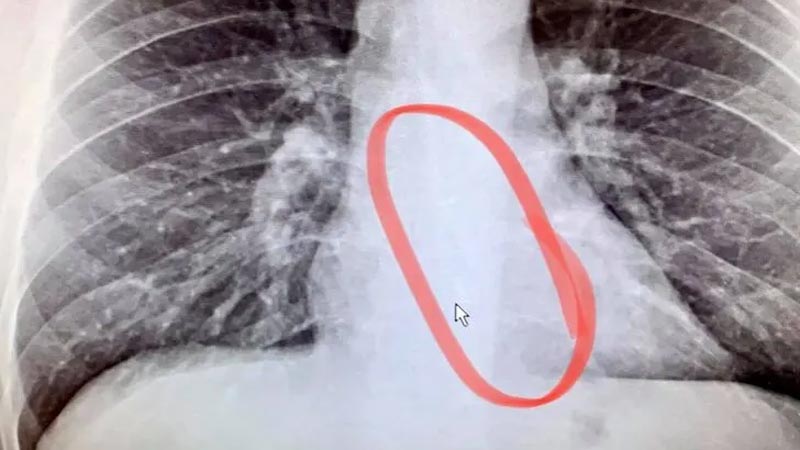

RÖNTGENDE TEKİNİ GÖRDÜ

Acil servise başvuran ABD’li adam, hastaneye gittiğinde gerçeği öğrendi. Gauthier’ın aklını kemiren düşünce doğru çıktı. Hastanede çektirdiği röntgen filminde Gauthier, kaybolan kulaklığın tekini yemek borusunda buldu. Yemek borusundaki kulaklık, hemen endoskopi ile Gauthier’ın yemek borusundan çıkartıldı.